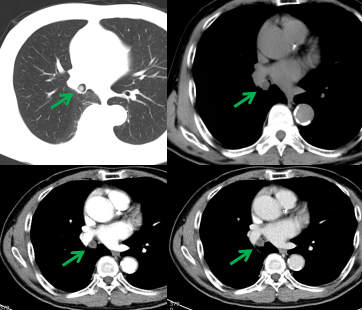

老年男性,體檢胸部CT檢查發(fā)現(xiàn)右肺中間段支氣管及右肺中葉支氣管不通暢,右肺中葉肺不張,右肺下葉炎癥?;颊邿o咳嗽、咳痰、胸悶、氣短、咯血等不適,飲食、睡眠可,大小便無異常,近期體重?zé)o明顯下降。既往有“高血壓”“心臟早搏”病史,吸煙30余年,每日1包,無飲酒嗜好。腫瘤標(biāo)志物無明顯異常。完善胸部強(qiáng)化CT檢查提示支氣管腔內(nèi)腫瘤,建議支氣管鏡檢查(圖1)。

圖1,右肺中間段支氣管結(jié)節(jié)(綠箭),增強(qiáng)掃描輕度強(qiáng)化。